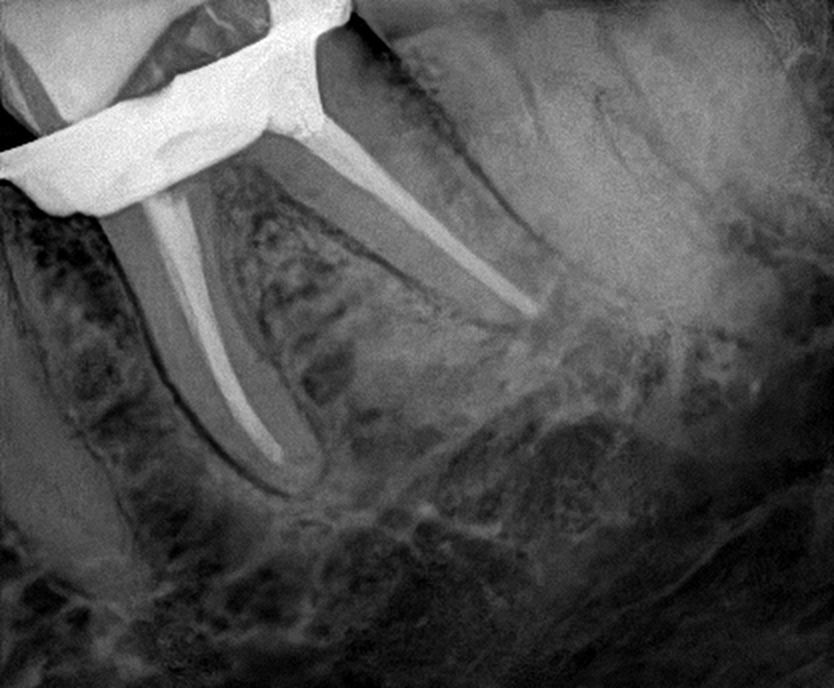

Fotos y videos